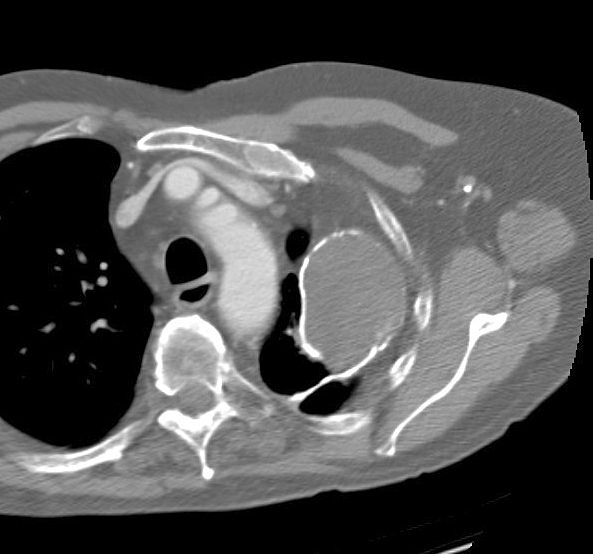

Gallery Pleural calcified emp CT

calcified emp CT